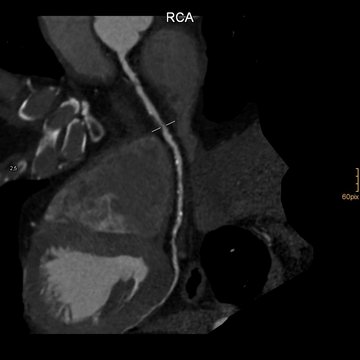

Darstellung der rechten Herzkranzarterie. Es kann die Gefäßwand und das Lumen präzise dargestellt werden.